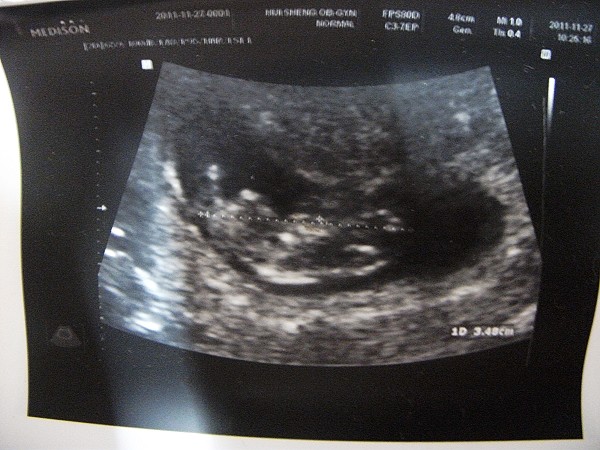

100.11.27「11w+4」

醫生照了一下魏啊啊的狀況

很好很好~阿木雖然又咳又流鼻水的

魏啊啊在肚子裡已經開始又踢又吃手指頭了

看到變成人形的魏啊啊

之前許許多多的不安似乎更加放下心了